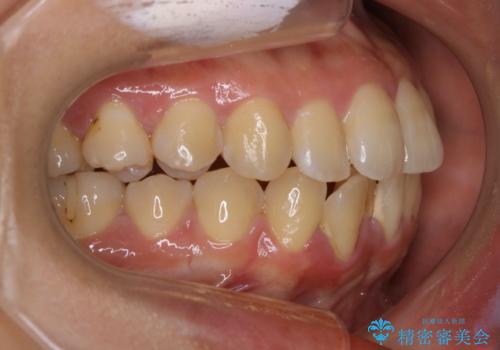

- 前歯を後ろへ下げることを主訴に来院された患者様です。

10代の時に非抜歯でワイヤー矯正をしていました。

口元の突出感の改善や歯の移動量などを考慮し、抜歯を伴うワイヤー矯正での治療を選択しました。

抜歯を行うことで前歯を後ろへ下げるスペースを獲得し、口元の突出感や歯のガタつきを改善していきました。